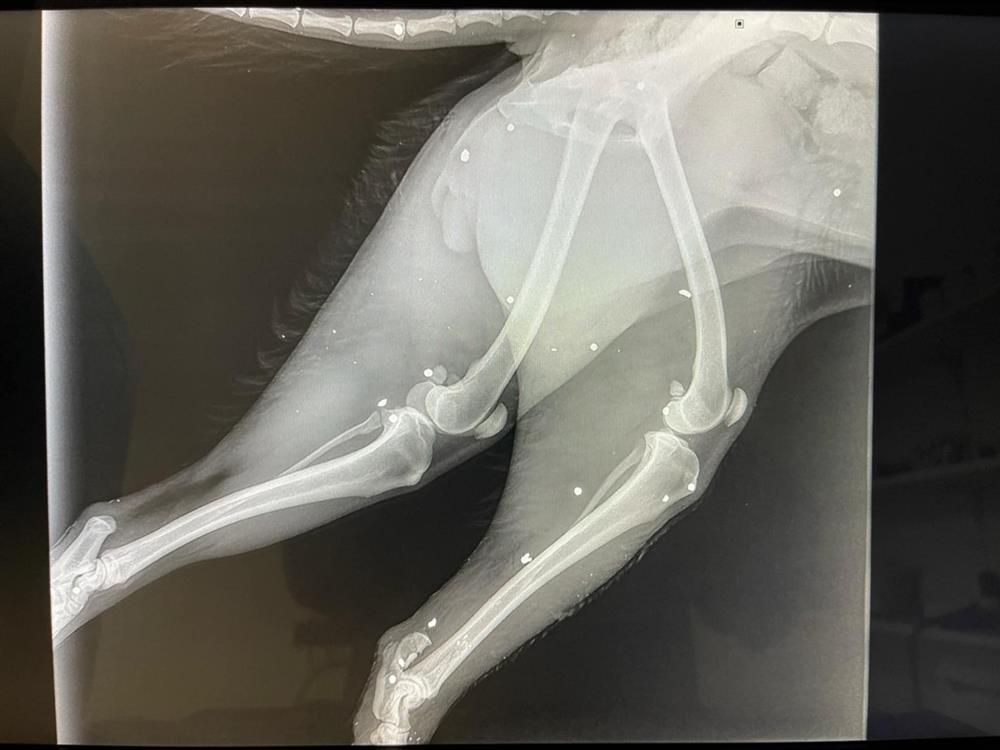

Ένα αποτρόπαιο περιστατικό κακοποίησης ζώου σημειώθηκε στο Αρκαλοχώρι του Δήμου Μινώα Πεδιάδας, στο Ηράκλειο, προκαλώντας σοκ και αγανάκτηση. Σύμφωνα με πληροφορίες, άγνωστος δράστης φέρεται να επιτέθηκε σε ένα μικρόσωμο σκυλάκι, προκαλώντας του σοβαρά τραύματα στα άκρα. Σαν να μην έφτανε αυτό, στη συνέχεια το πυροβόλησε, ολοκληρώνοντας την αποτρόπαια πράξη του.

Οι κτηνίατροι δεν κατάφεραν να σώσουν το ένα πόδι της σκυλίτσας, με αποτέλεσμα να προχωρήσουν σε ακρωτηριασμό, ενώ της τοποθέτησαν και νάρθηκα. Περαστικοί το βρήκαν στην άκρη του δρόμου να ουρλιάζει από τους φρικτούς πόνους.